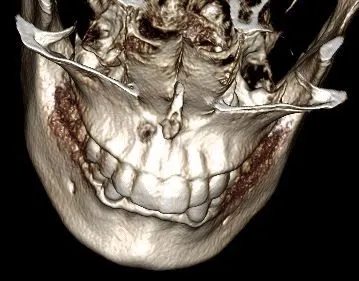

Case3